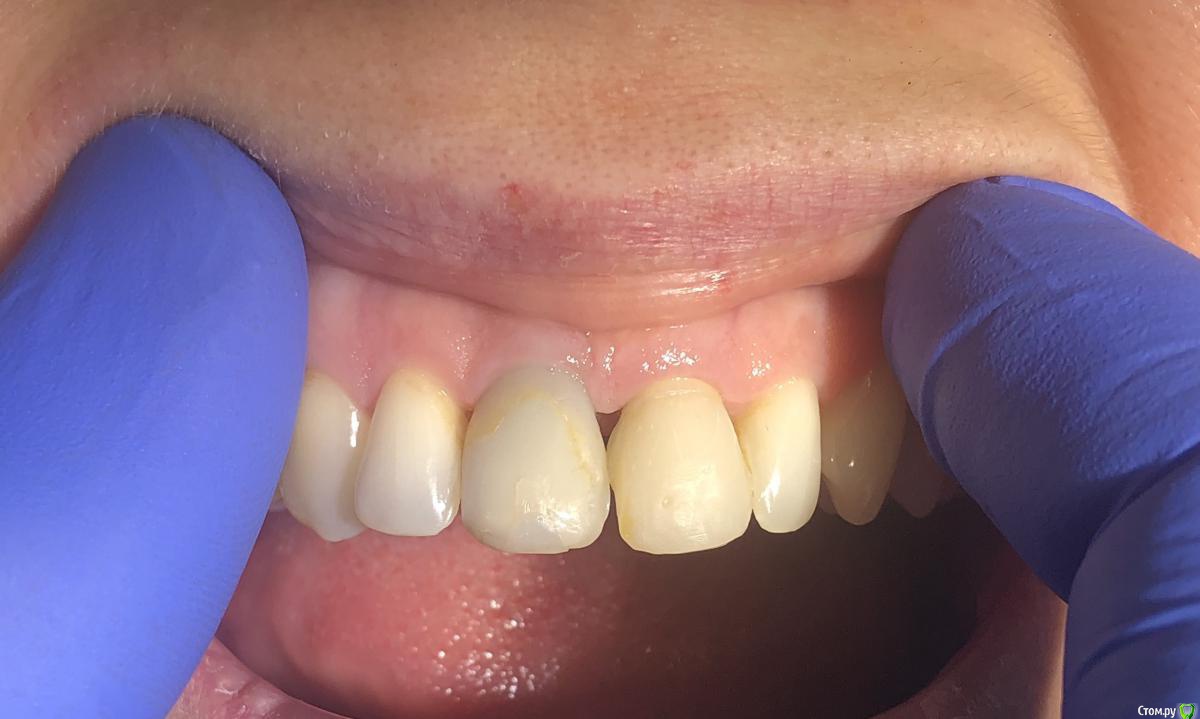

Александр07 Опубликовано 26 июня, 2020 Автор Поделиться Опубликовано 26 июня, 2020 Коллеги, скидываю фото проделанной работы, прошло около 1.5 мес, есть результат, спасибо за помощь, если какие то замечания /советы есть пишите 4 Ссылка на комментарий

Irouil Опубликовано 26 июня, 2020 Поделиться Опубликовано 26 июня, 2020 Справились одним трансплантом в итоге?) Ссылка на комментарий

Александр07 Опубликовано 27 июня, 2020 Автор Поделиться Опубликовано 27 июня, 2020 Справились одним трансплантом в итоге?)Два, один под сосочек с бугра второй вестибулярно с неба Сст 1 Ссылка на комментарий